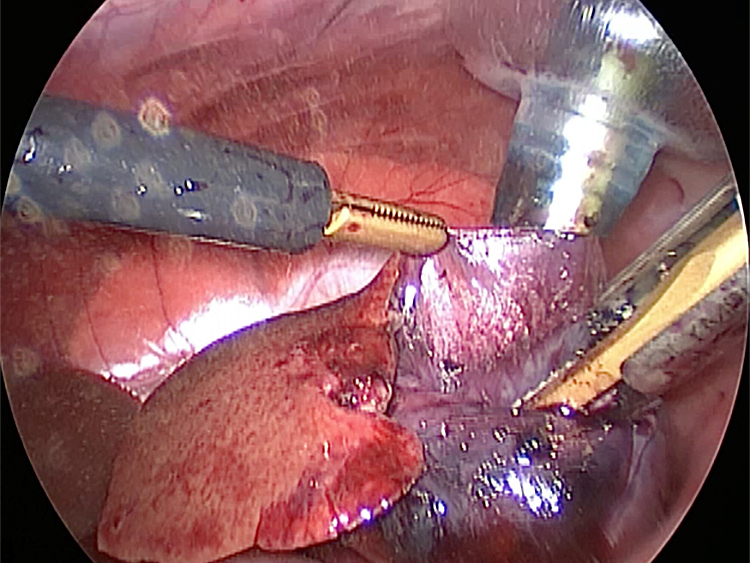

胆嚢の周囲の脂肪や膵臓、十二指腸が激しく癒着し剥離が困難な状態でした。胆嚢は全く確認することができませんでした。

少しずつ癒着を剥がして胆嚢が確認できるようになってきました。 こんなに癒着していることはあまりないので過去に膵炎や胆嚢炎を起こし苦しい時期があったことが推測されました。 それにしてもなかなか胆嚢はでてきませんでした。

癒着(矢印)がひどく胆嚢を確認することができませんでした。 このように癒着しているときはギリギリで剥がすとひどく出血をおこすことがあるので無理にはがそうとしないで、脂肪の血管に注意しながら脂肪ごと剥がしていきます。

胆嚢(矢印)の取り囲むように肝臓や腸が癒着していました。肝臓の表面はボコボコしています。